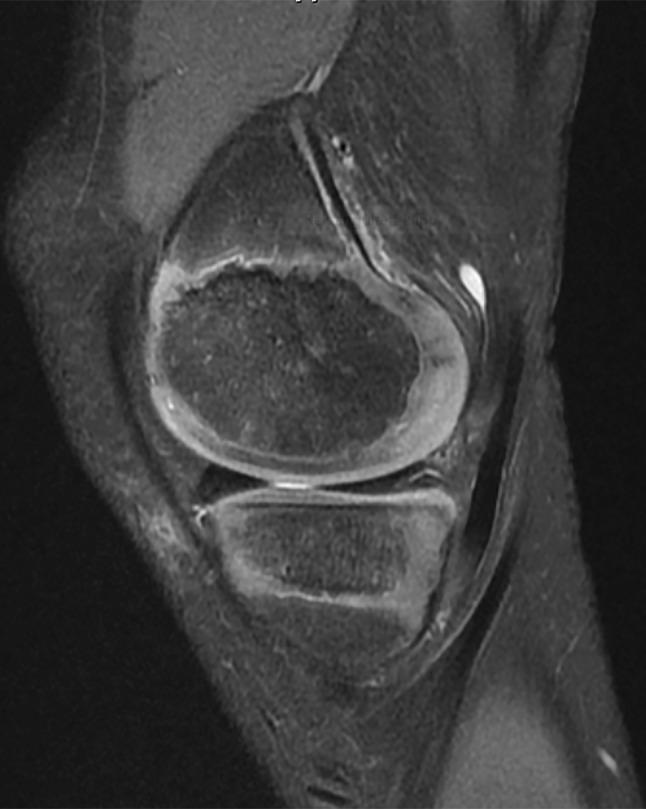

In October 2017, the International Olympic Committee hosted an international expert group of physiotherapists and orthopaedic surgeons who specialise in treating and researching paediatric anterior cruciate ligament (ACL) injuries. Representatives from the American Orthopaedic Society for Sports Medicine, European Paediatric Orthopaedic Society, European Society for Sports Traumatology, Knee Surgery and Arthroscopy, International Society of Arthroscopy Knee Surgery and Orthopaedic Sports Medicine, Pediatric Orthopaedic Society of North America, and Sociedad Latinoamericana de Artroscopia, Rodilla y Deporte attended. Physiotherapists and orthopaedic surgeons with clinical and research experience in the field, and an ethics expert with substantial experience in the area of sports injuries also participated. Injury management is challenging in the current landscape of clinical uncertainty and limited scientific knowledge. Injury management decisions also occur against the backdrop of the complexity of shared decision-making with children and the potential long-term ramifications of the injury. This consensus statement addresses six fundamental clinical questions regarding the prevention, diagnosis, and management of paediatric ACL injuries. The aim of this consensus statement is to provide a comprehensive, evidence-informed summary to support the clinician, and help children with ACL injury and their parents/guardians make the best possible decisions.

2017 年 10 月,国际奥林匹克委员会举办了一次国际专家组会议,参会者包括专门治疗和研究儿科前交叉韧带(ACL)损伤的物理治疗师和骨科医生。美国运动医学骨科协会、欧洲儿科骨科协会、欧洲运动创伤学、膝关节外科和关节镜学会、国际关节镜膝关节外科和骨科运动医学学会、北美小儿骨科协会和拉丁美洲关节镜、膝盖和运动医学协会的代表出席了会议。具有该领域临床和研究经验的物理治疗师和骨科医生,以及一位在运动损伤领域有丰富经验的伦理专家也参与了会议。在目前临床不确定性和有限科学知识的背景下,损伤管理具有挑战性。损伤管理决策还需要考虑与儿童共同决策的复杂性,以及损伤的潜在长期后果。本共识声明针对儿科 ACL 损伤的预防、诊断和管理提出了六个基本的临床问题。本共识声明的目的是提供全面、循证的总结,以支持临床医生,并帮助 ACL 损伤患儿及其父母/监护人做出尽可能最好的决策。